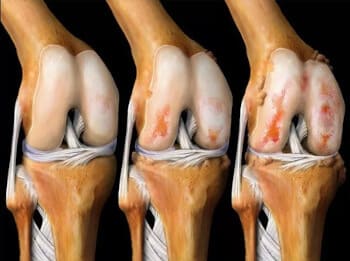

মনে রাখবেন: আর্থ্রাইটিস এবং আর্থ্রোসিস 3 বছরে কার্টিলাজিনাস টিস্যু ধ্বংস করে! দুর্ভাগ্যবশত, আর্থ্রাইটিসের জন্য কোন ওষুধ নেই, শুধুমাত্র একটি অপারেশন আপনাকে সাহায্য করতে পারে...

হাঁটু জয়েন্টের তরুণাস্থির উপর অস্টিওআর্থারাইটিসের প্রভাব।